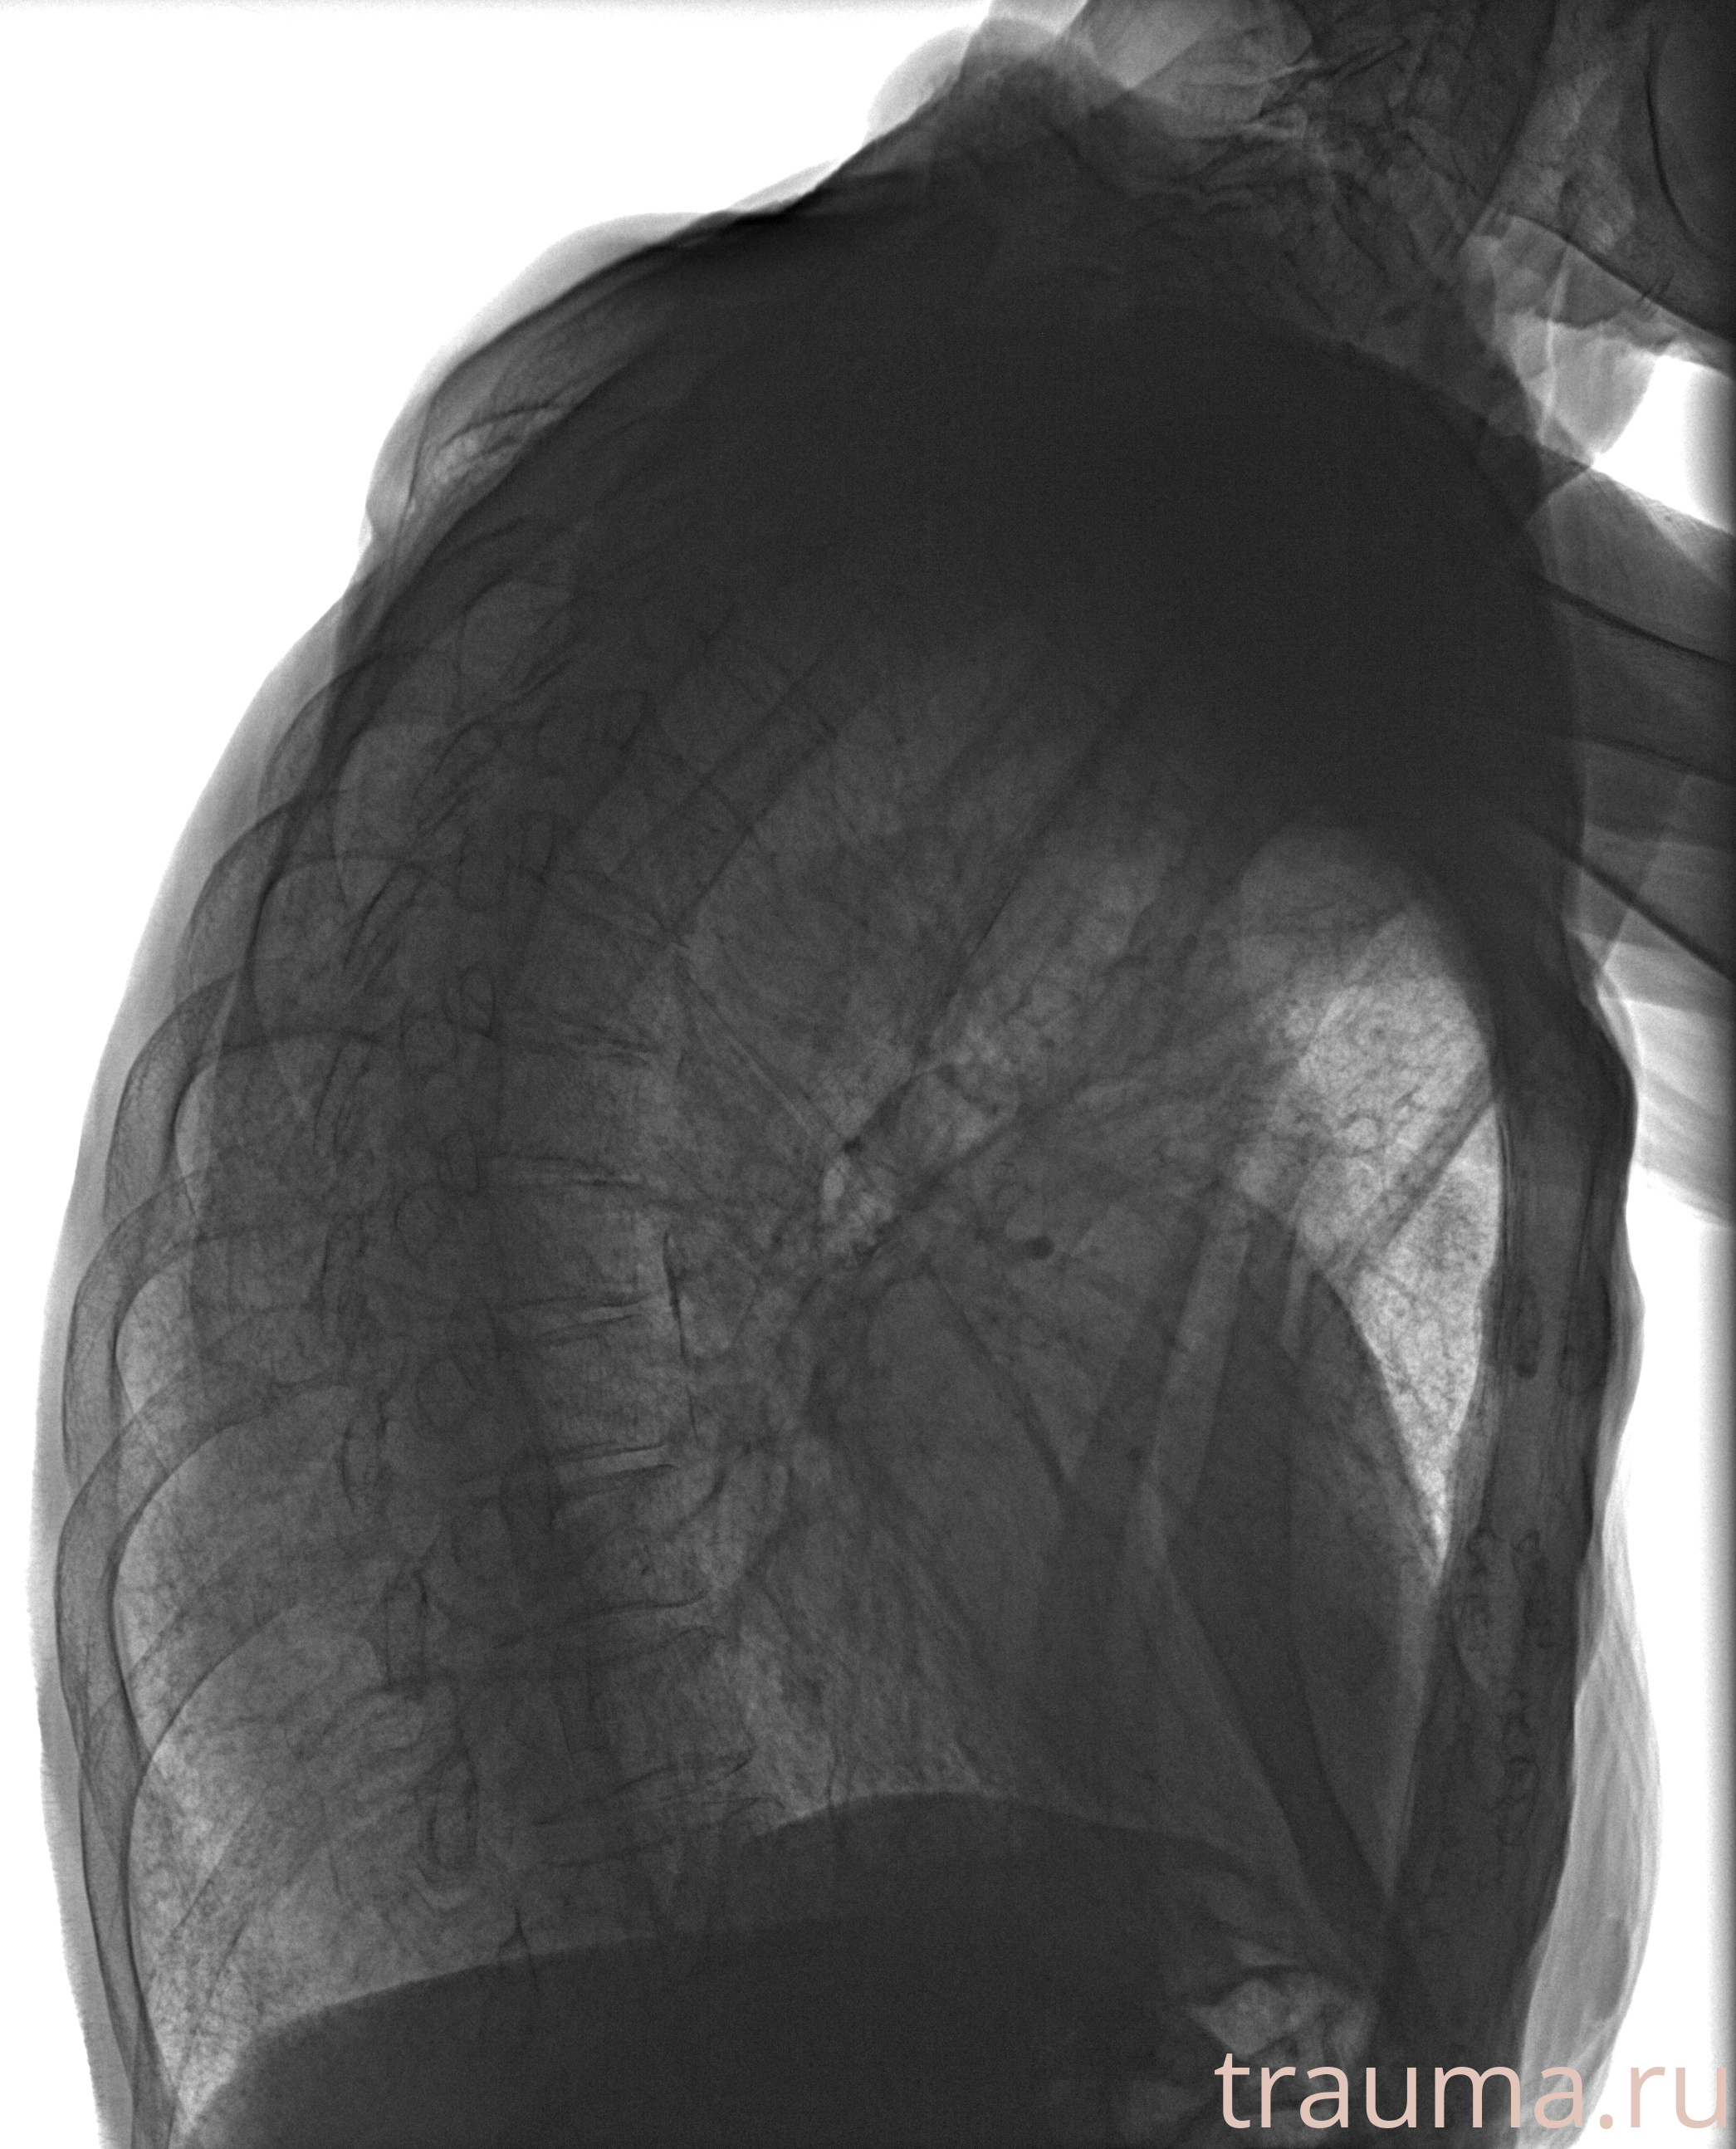

Рентген на дому: по вашему адресу приезжает врач-рентгенолог, травматолог-ортопед с мобильным рентгеновским аппаратом, проводит диагностику травмы или заболевания, делает необходимые рентгенограммы, дает рекомендации по дальнейшему лечению. Получить качественные снимки в домашних условиях возможно благодаря уникальной методике, разработанной МосРентген Центром для института  Склифосовского

при переломе шейки бедра и пневмонии от компании МосРентген Центр - партнера Института имени Склифосовского